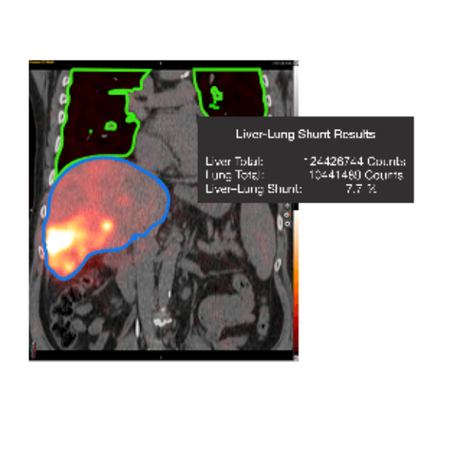

- Calculate liver-lung shunt fraction from both planar and SPECT images.